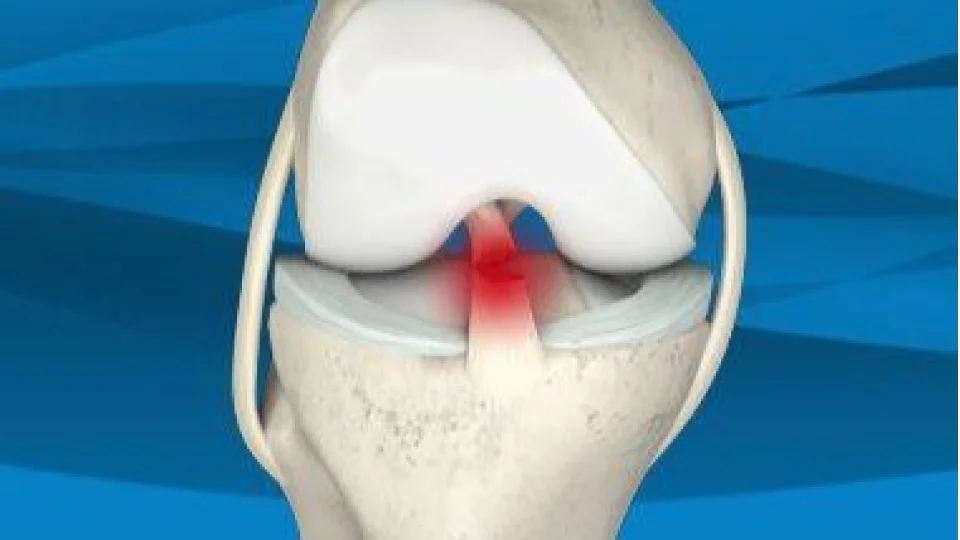

Menisküs, diz ekleminde "C" şeklinde yer alan kıkırdak yapıdır ve vücut ağırlığını dengeli dağıtarak ekleme binen baskıyı azaltır. Ancak ani hareketler, spor sırasında yapılan bilinçsiz uygulamalar ve yaşa bağlı yıpranmalar bu yapının yırtılmasına neden olabilir.

Yırtığın Özellikleri

Menisküsün dış kısmındaki küçük yırtıklar bazen kendiliğinden iyileşebilirken, iç kısımdaki yırtıkların veya büyük ve karmaşık yırtıkların iyileşme olasılığı düşüktür. Bu nedenle tedavi planı yırtığın büyüklüğü, yeri ve tipi dikkate alınarak yapılır.